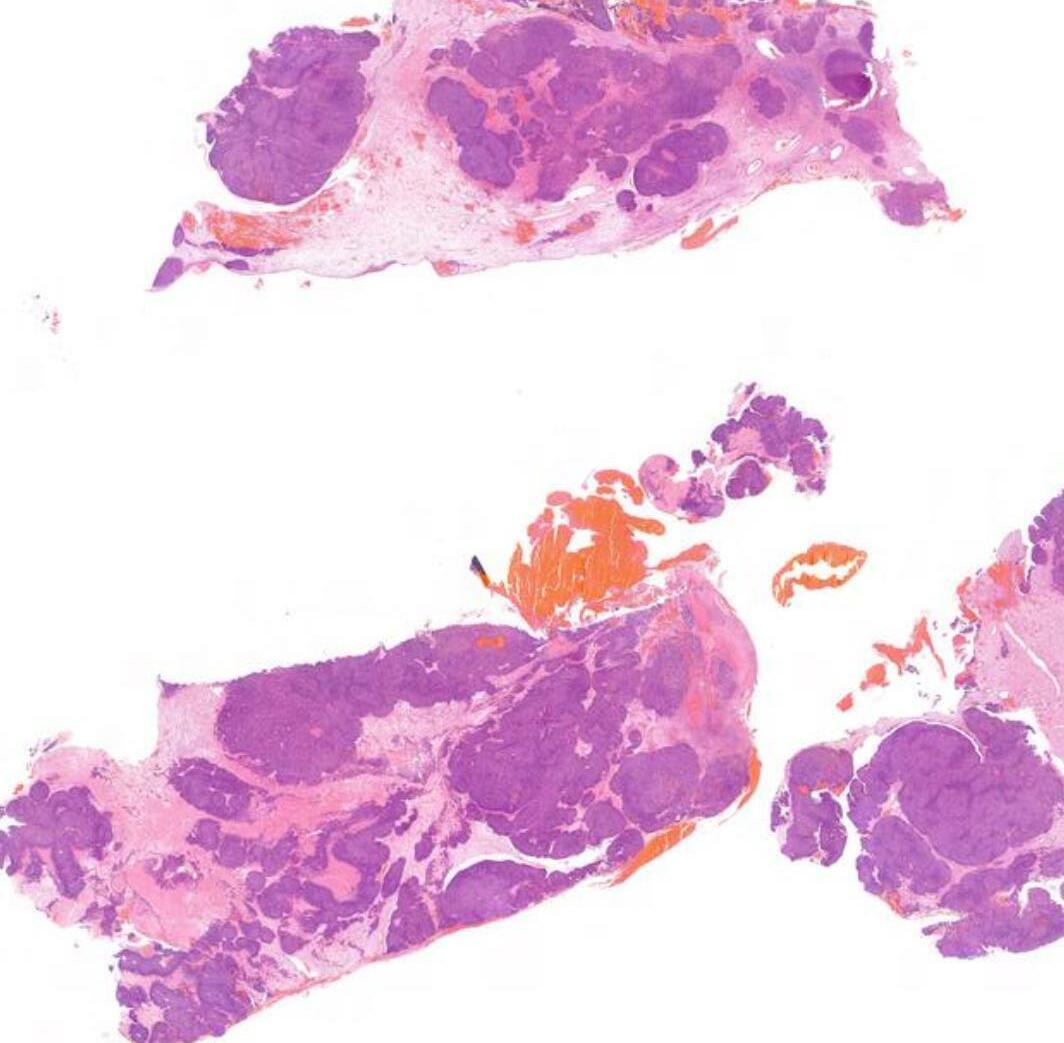

26-year-old, Female, Parotid tumour

Case 1- Salient points • Circumscribed salivary tumour, infiltrative periphery • Papillary cystic, microcystic patterns, hobnailing • Solid sheets of large polygonal cells with granular eosinophilic cytoplasm and vesicular nuclei • Secretory material –colloid-like eosinophilic secretions • Occasional mitotic figures • Work up? PAS, DPAS, • CK7, S100, DOG1, Mammoglobin

Case 1 Diagnosis

Secretory carcinoma

Discussion Differential diagnoses • Acinic cell carcinoma • Secretory carcinoma (previously called MASC) • MEC • 90% -ETV6::NTRK3 fusion -chromosomal rearrangement, t(12;15) (p13;q25) • ETV6::RET, ETV6::MET, ETV6::MAML3 • ETV6 translocation-negative secretory carcinoma. • Similar to Acinic cell carcinoma • But S100+, Mammoglobin+, DOG1-